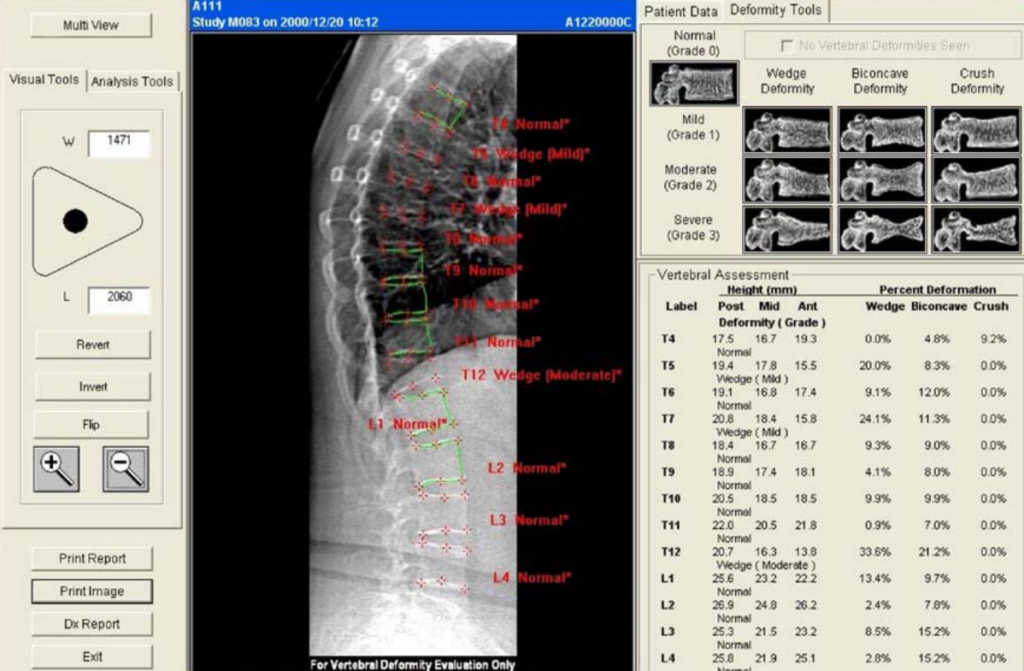

Il radiologo o l’operatore specializzato esamina le vertebre da T4 a L4 e assegna a ciascuna un punteggio di gravità basato sulla riduzione percentuale dell’altezza vertebrale rispetto all’altezza di riferimento (solitamente l’altezza posteriore della stessa vertebra o l’altezza di una vertebra adiacente sana).

| Grado di frattura | Riduzione % dell’altezza | Descrizione clinica |

|---|---|---|

| Grado 0 | <20% | Vertebra normale |

| Grado 1 (lieve) | 20−25% | Frattura lieve (spesso asintomatica) |

| Grado 2 (moderato) | 25−40% | Frattura moderata (impatto biomeccanico) |

| Grado 3 (grave) | >40% | Frattura severa o collasso totale |

La misurazione quantitativa computerizzata automatizza questo processo posizionando sei punti (reperi) su ogni corpo vertebrale, calcolando istantaneamente i rapporti tra le altezze anteriore, centrale e posteriore.

Sebbene la misurazione automatica sia rapida, la supervisione del radiologo è indispensabile per confermare la natura osteoporotica della deformità e non confonderla con varianti anatomiche o processi degenerativi.